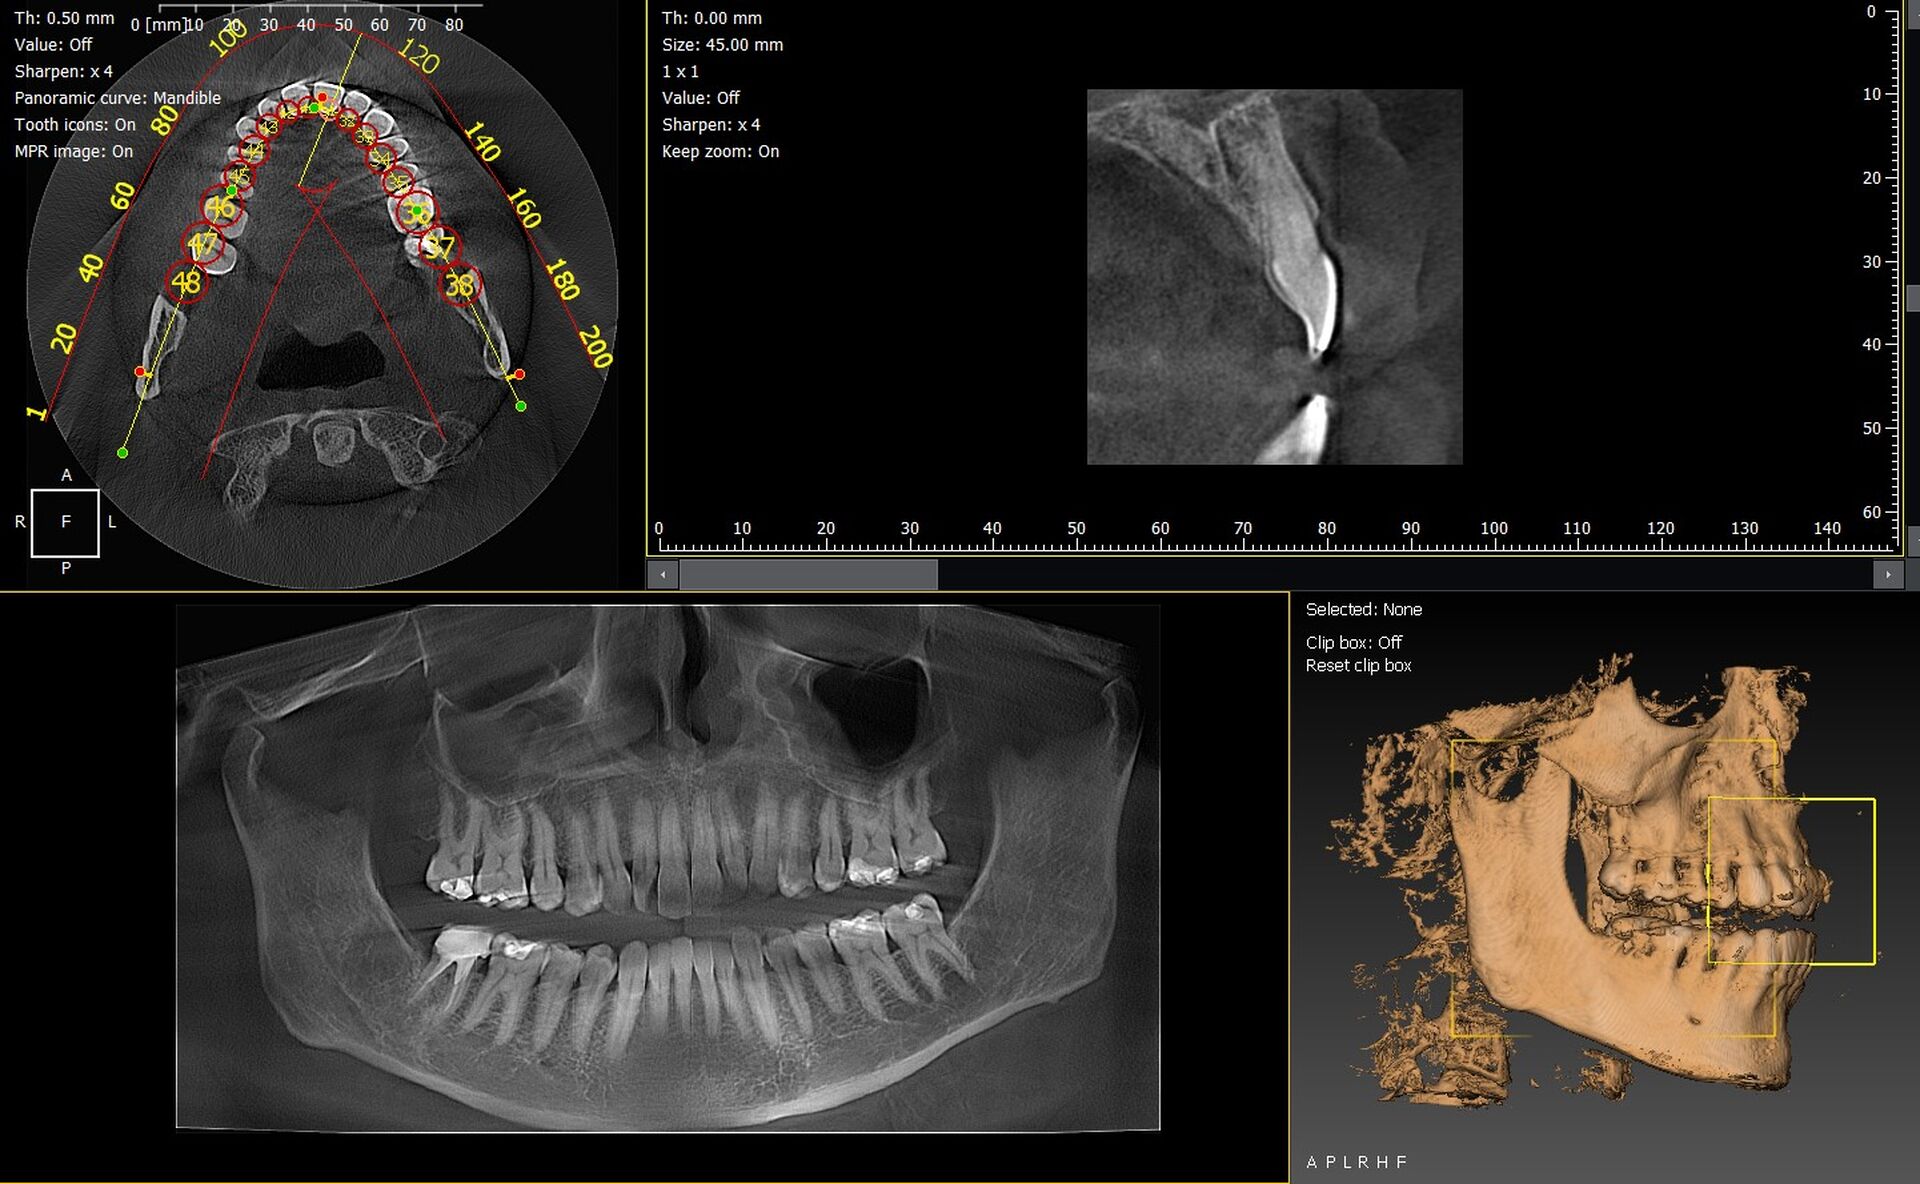

Les cabinets dentaires d’Aix-en-Provence et du département des Bouches-du-Rhône (13) modernisent leur plateau technique grâce à des solutions d’imagerie 3D performantes et fiables. Les panoramiques CBCT 3D VistaVox de Dürr Dental et l’Owandy I-Max 3D comptent parmi les systèmes les plus avancés du marché, garantissant une qualité d’image exceptionnelle et un diagnostic précis.

VistaVox 3D : précision et volume optimisé

Le VistaVox offre :

• un volume d’exploration idéal pour l’arcade dentaire,

• une très haute résolution pour l’implantologie et l’endodontie,

• une réduction de dose maîtrisée,

• un positionnement patient rapide et ergonomique.